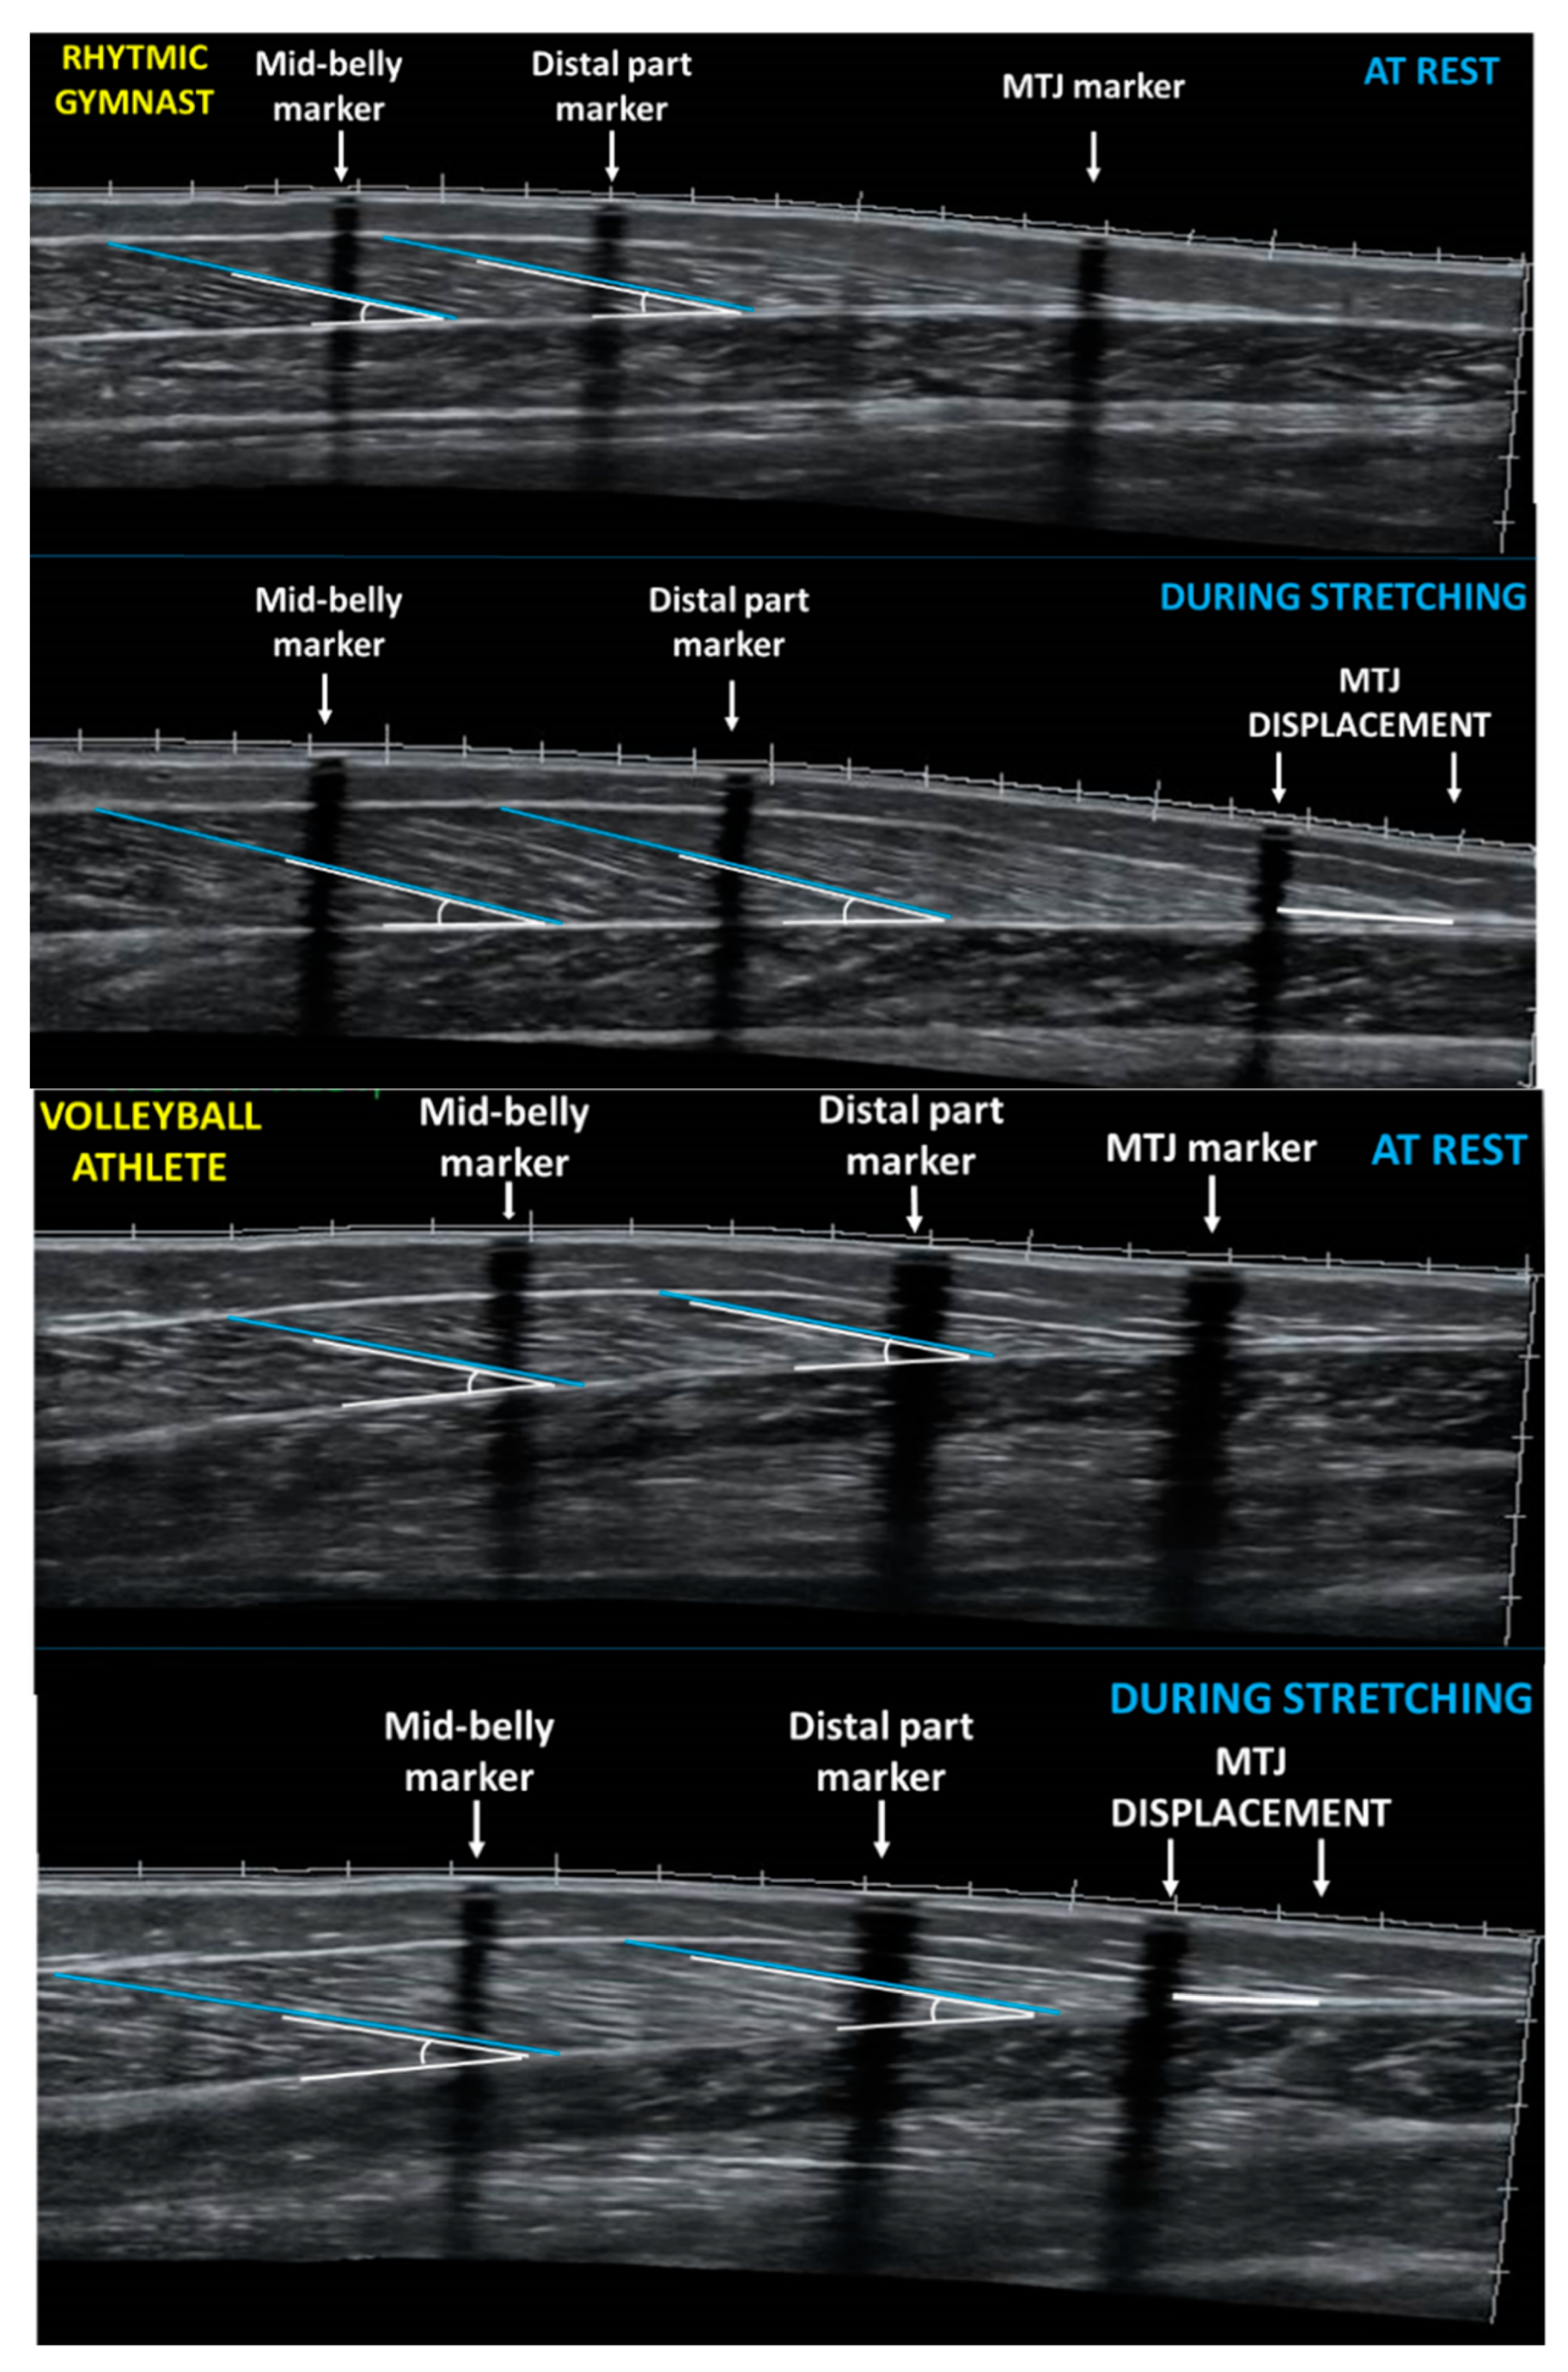

2.3. Gastrocnemius Medialis Architecture and Ankle Joint Angle at Rest

2.4. Gastrocnemius Medialis Architecture and Ankle Joint Angle during Ankle Dorsiflexion Stretching